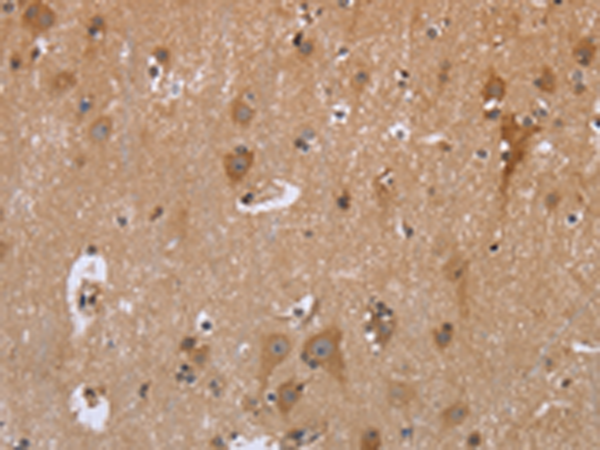

分类: 科研抗体货号: P01447别名: HDL; 11-DH; HSD11; HSD11B; HSD11L; CORTRD2; SDR26C1; 11-beta-HSD1应用: IHC反应种属: Human